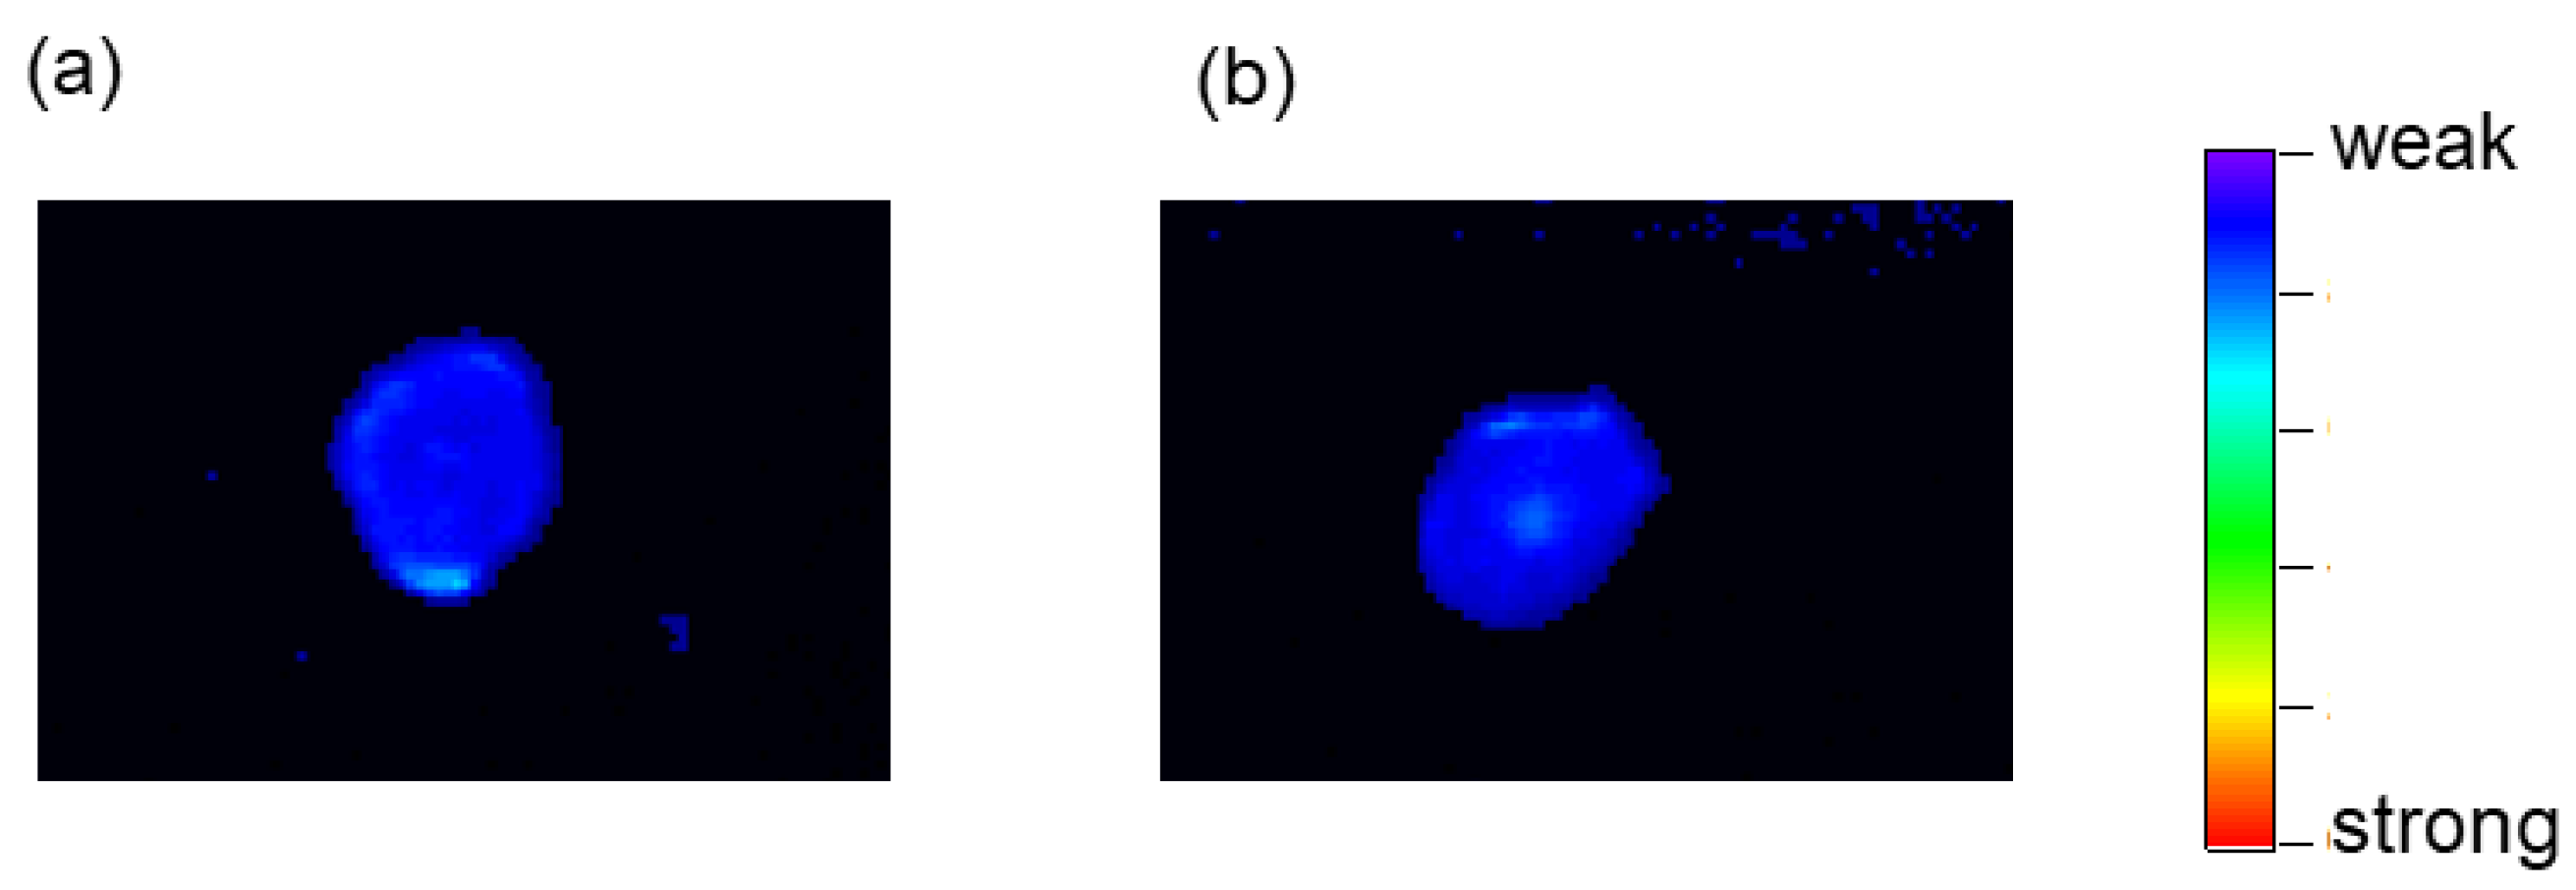

2.6. Tumor-Imaging with TFMAQ-diEg4